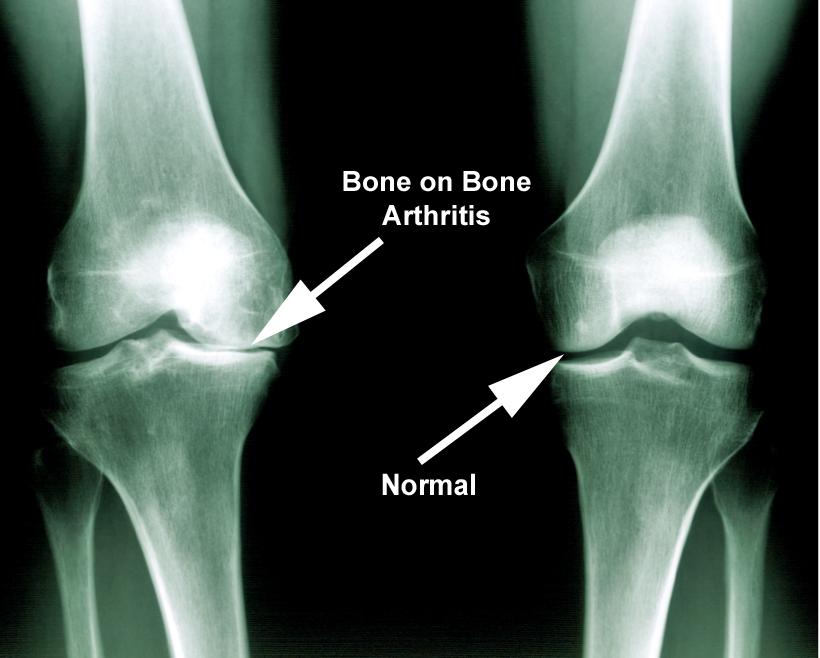

Joint pain is often caused by:

- Cartilage breakdown (osteoarthritis)

Many traditional treatments only provide temporary relief and don’t address these underlying issues.